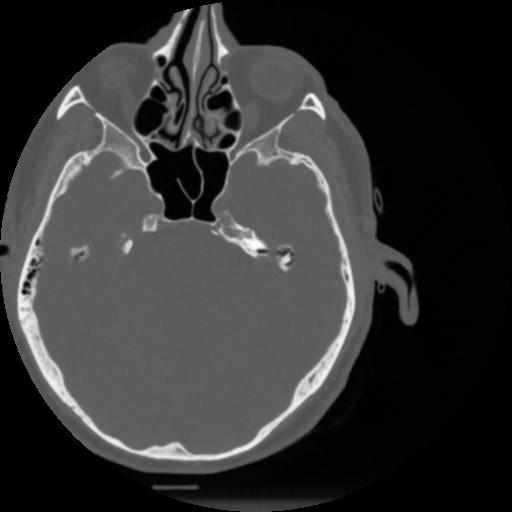

4 CEREBRO,,Vol,0.5,CEREBRO,,